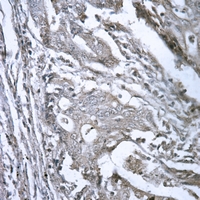

Immunohistochemical analysis of GDF1 staining in human colorectal cancer formalin fixed paraffin embedded tissue section. The section was pre-treated using heat mediated antigen retrieval with sodium citrate buffer (pH 6.0). The section was then incubated with the antibody at room temperature and detected using an HRP conjugated compact polymer system. DAB was used as the chromogen. The section was then counterstained with haematoxylin and mounted with DPX.